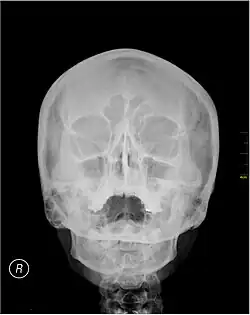

Waters' view (also known as the occipitomental view or parietoacanthial projection) is a radiographic view of the skull. It is commonly used to get a better view of the maxillary sinuses. An x-ray beam is angled at 45° to the orbitomeatal line. The rays pass from behind the head and are perpendicular to the radiographic plate. Another variation of the waters places the orbitomeatal line at a 37° angle to the image receptor. It is named after the American radiologist Charles Alexander Waters.

Waters' view can be used to best visualise a number of structures in the skull.

- Maxillary sinuses.

- Frontal sinuses, seen with an oblique view.

- Ethmoidal cells.

- Sphenoid sinus, seen through the open mouth.

- Odontoid process, where if it is just below the mentum, it confirms adequate extension of the head.

Typically, the x-ray beam is angled at 45° to the orbitomeatal line.[3] Another variation of the waters places the orbitomeatal line at a 37° angle to the image receptor,[4] or 30°.[5]